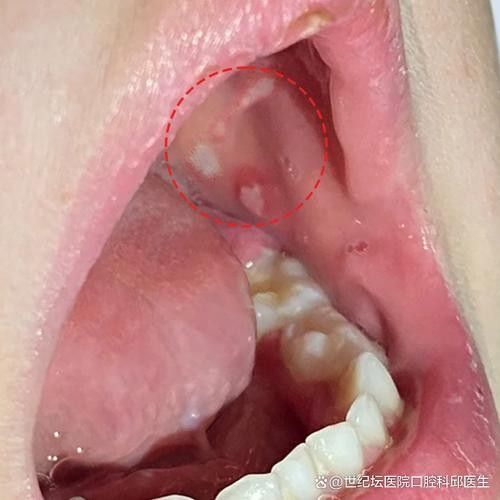

嘴角內側的肉芽可能是由多種原因引起的,包括感染、過敏反應、外傷或某些疾病,這些肉芽通常呈現為柔軟、紅色或紫色的小突起,有時伴有輕微的疼痛或不適感,如果寶寶出現這樣的癥狀,家長應立即帶寶寶就醫,以便醫生進行詳細的檢查和診斷。,在等待就醫的過程中,家長可以采取一些措施來緩解寶寶的不適,保持寶寶的嘴巴清潔,避免食用刺激性食物,以及使用適當的口腔護理產品,家長還應密切觀察寶寶的癥狀變化,如有惡化或出現其他異常情況,應及時就醫。,寶寶嘴角內側的肉芽可能是一個需要關注的問題,家長應密切關注寶寶的癥狀變化,并在必要時尋求專業根據您提供的參考信息,寶寶嘴角內側出現肉芽狀組織可能涉及多種情況,以下為常見原因及對應的特征描述12:

口腔黏膜(包括嘴角內側)可能出現腫脹、分葉狀或增厚腫大的組織,表面光滑或有小結節,易被咬傷形成潰瘍1。

展開黏液腺囊腫

多見于口腔兩側,表現為半透明、質軟有彈性的小皰,可能因咬破后流出黏稠液體,可反復生長2。生理性因素(如馬牙)

嬰幼兒牙板殘留的角質化組織可能形成對稱分布的白色小顆粒,通常數周后自行消退,無需治療3。皰疹病毒感染或鵝口瘡

- 皰疹病毒:成簇透明水皰,可能伴隨疼痛3。

- 鵝口瘡:乳白色似奶塊的斑塊,多由真菌感染引起3。